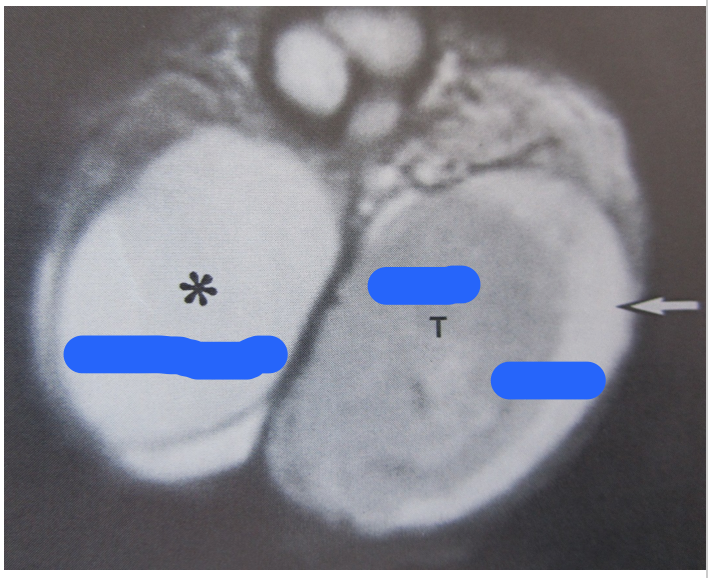

What do the letters represent?